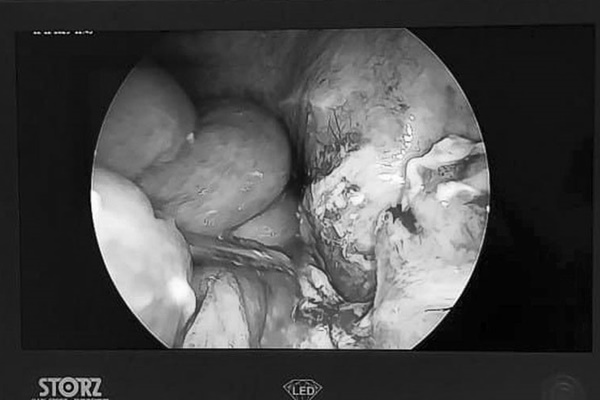

Bác sĩ chuyên khoa tiêu hóa tại bệnh viện đã yêu cầu bệnh nhân siêu âm B và các cuộc kiểm tra liên quan khác, phát hiện có dị vật trong ruột thừa. Để tìm cách điều trị, bệnh nhân được chuyển sang Khoa Nội soi.

Tại đây, người ta phát hiện dị vật bên trong hóa ra là hạt dưa hấu. Dị vật gây viêm ruột thừa phần lớn là sỏi phân nằm trong khoang ruột thừa và không thể tiêu hóa được. Sau ca phẫu thuật, bệnh nhân ngay lập tức cảm thấy cơn đau bụng giảm bớt, nhanh chóng trở lại chế độ ăn uống bình thường và được xuất viện. Chàng trai cũng rất ngạc nhiên khi thủ phạm gây ra bệnh viêm ruột thừa lại là một nắm hạt dưa hấu.